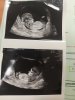

Jedyny pozytywny test miałam pod koniec 2011 roku, wtedy udało mi się zajść w ciążę naturalnie, którą poroniłam w 8/9tyg, ale od początku zarodek nie rozwijał się prawidłowo. Od tamtej pory nic...